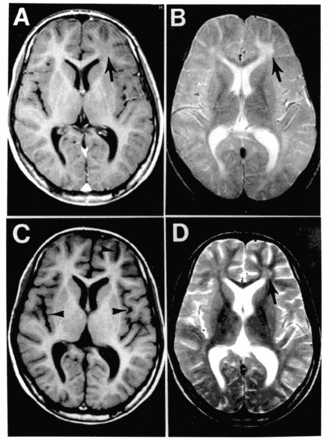

![]() Imágenes de resonancia magnética del cerebro en el momento de la presentación en la consulta de neurología (A y B) y 3 meses después (C y D). Los paneles A y C son imágenes ponderadas en T1; B y D son imágenes ponderadas en T2. La resonancia magnética inicial (A y B) revela una anomalía focal en la sustancia blanca subcortical del lóbulo frontal izquierdo, que consiste en una señal hipointensa en la imagen ponderada en T1 (flecha en A) y una señal hiperintensa en la imagen ponderada en T2 (flecha en B). En la gammagrafía de seguimiento, la anomalía focal en el lóbulo frontal izquierdo es menos evidente que antes (flecha en D), pero está presente una atrofia cortical avanzada y difusa, representada por ventriculomegalia y surcos marcadamente agrandados (puntas de flecha en C). | ||